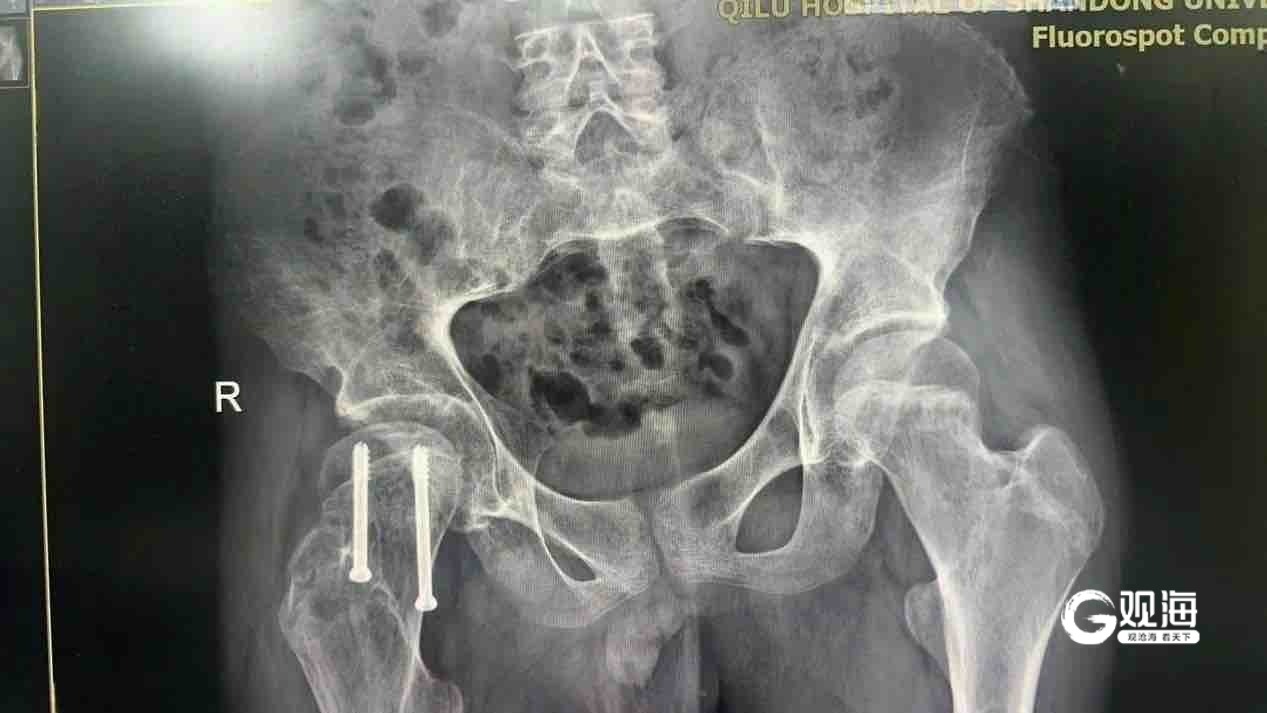

面对如此复杂的病情,山东大学齐鲁医院(青岛)小儿骨科的医疗团队展现出了高超的专业水平。在多学科会诊后,他们制定了详细的治疗方案,并由许洪涛主刀完成了右股骨头骨骺滑脱闭合空心钉内固定术。术后,艾先生的疼痛症状得到了明显的缓解,活动能力也有所恢复,预后良好。